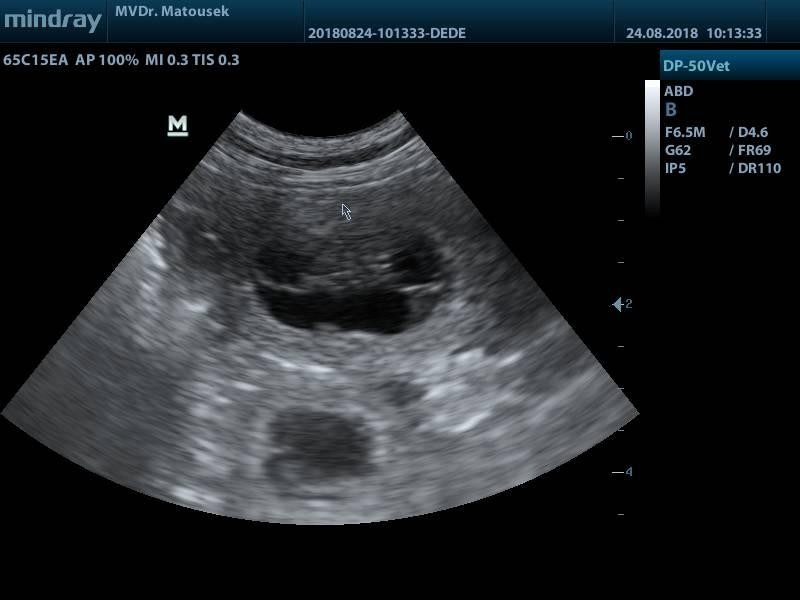

Na sonografické vyšetření jsem měla s Banshee jít až v pondělí, ale nějak jsem to nevydržela.. Navíc Bandaska je poměrně čitelná, vlastně jsem si jen šla potvrdit to, co již čtyři týdny tuším - je březí a čeká štěňátka. Poslední dny jí začínají pravé "těhotenské" problémy, nechutenství, apatie, lenost, rozladěnost. Naštěstí rychle pominou (stejně jako posledně) a Bandasku budu muset silně krotit v jídle, aby nebyla jako sud :) To všechno známe, to všechno už tady jednou bylo. Co se týká počtu štěňátek, když se pan doktor dopočítal k číslu sedm, dál už jsme nic nezkoumali - prostě jak to vyjde, tak to bude.

Dnešní foto je sonografický snímek a oba budoucí rodiče